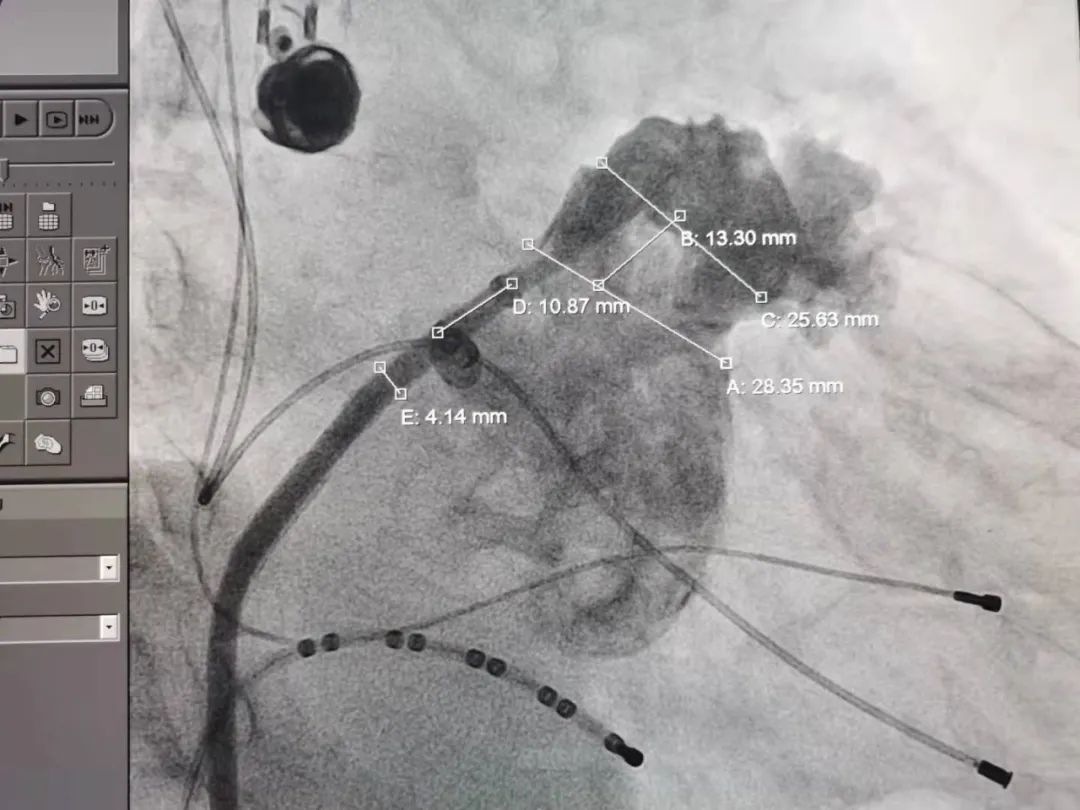

左心耳头位造影

左心耳测量

常规肝位造影显示,左心耳锚定区约26mm, 开口约29mm, 因此选择型号为LT-LAA-2834的LAmbre™左心耳封堵器对患者实施封堵。LAmbre™植入过程一步到位,U型钩均完全展开。随后复查造影及TEE结果,封堵盘呈“碗状”形态完美贴合于左心耳口部,无残余分流,牵拉测试稳定,综合评估符合COST原则,随后完美释放,封堵效果理想。术后,患者各项指标正常,身体恢复良好。